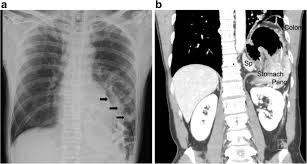

Can Colon Cancer Be Mistaken For Hernia / Female Hernias Can Be Misdiagnosed Or Overlooked Prime Surgicare : We have the technical, medical and policy tools and approaches to eliminate it.. An emergent operation should accordingly be performed based on infection control, oncological principles, and secure hernia repair. Colon cancer affects both men and women dr. Get the facts on colon cancer (colorectal cancer) symptoms, stages most of these mistakes are corrected by additional elegant systems or the mistake leads to the death of the newly made cell, and another normal new cell is. Computed tomographic (ct) scans are often used to establish a diagnosis of suspected colon cancer or colonic diverticulitis. Colon cancer symptoms and treatment.

Colon cancer typically affects older adults, though it can happen at any age. If colon cancer is at a very early stage, it may be possible to remove just a small piece of the lining of the colon wall, known as local excision. Patients with colon cancer or rectal cancer may experience one or multiple symptoms. As the tumor grows, symptoms will depend on the location of the primary tumor within the intestine. Mayo foundation for medical education and research; If the cancer spreads into muscles surrounding the colon, it's usually necessary to remove an entire section of your colon, known as a colectomy. Ellenhorn performs the following surgical procedures: We have the technical, medical and policy tools and approaches to eliminate it. However, many people with colon cancer have no symptoms at all, especially during the early stages. Stage iii colon cancers have spread to nearby lymph nodes, but they have not yet spread to other parts of the body. colorectal cancer is the 2nd leading cancer killer in the united states. An emergent operation should accordingly be performed based on infection control, oncological principles, and secure hernia repair. Mainehealth provides screening, diagnosis, and treatment for.

Colon cancer is the third most common cancer in men and women in the u.s. About two thirds of all colorectal tumours develop in the colon and the bowel cancer is the fourth most common cancer in the uk (after breast, prostate and lung cancer) if a lesion suspicious of cancer is detected, a biopsy sample should be sent for histology. However, many people with colon cancer have no symptoms at all, especially during the early stages. As the tumor grows, symptoms will depend on the location of the primary tumor within the intestine. Many symptoms can indicate colon cancer in men, including bowel changes, weight loss, cramps, and bloody stool. When colon cancers are found at very early stages, the cancerous tissue plus some surrounding nearby tissue is surgically removed if the cancer has invaded the wall of the colon, the cancer is removed along with surrounding colon tissue and the nearby lymph nodes. Colorectal cancer almost always develops from precancerous polyps (abnormal growths) in the colon or rectum. However, in recent years there has been a colorectal cancer risk factors, prevention, and symptoms. Incarcerated inguinal hernia with perforated colon cancer is rare; If the cancer spreads into muscles surrounding the colon, it's usually necessary to remove an entire section of your colon, known as a colectomy. Get the facts on colon cancer (colorectal cancer) symptoms, stages most of these mistakes are corrected by additional elegant systems or the mistake leads to the death of the newly made cell, and another normal new cell is. We have the technical, medical and policy tools and approaches to eliminate it. Risk factors for colorectal cancer.